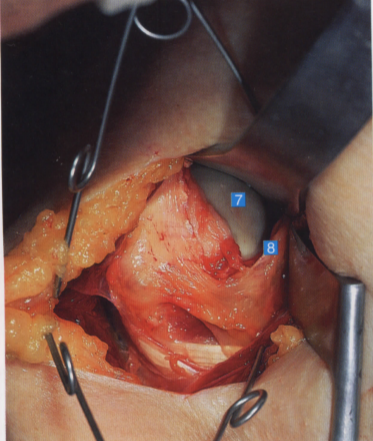

切开关节囊,显露出肱骨头及肩关节

6. 肩胛下肌筋膜;7. 肱骨头;

8. 肩胛下肌和关节囊;9. 肱神经;10. 腋神经